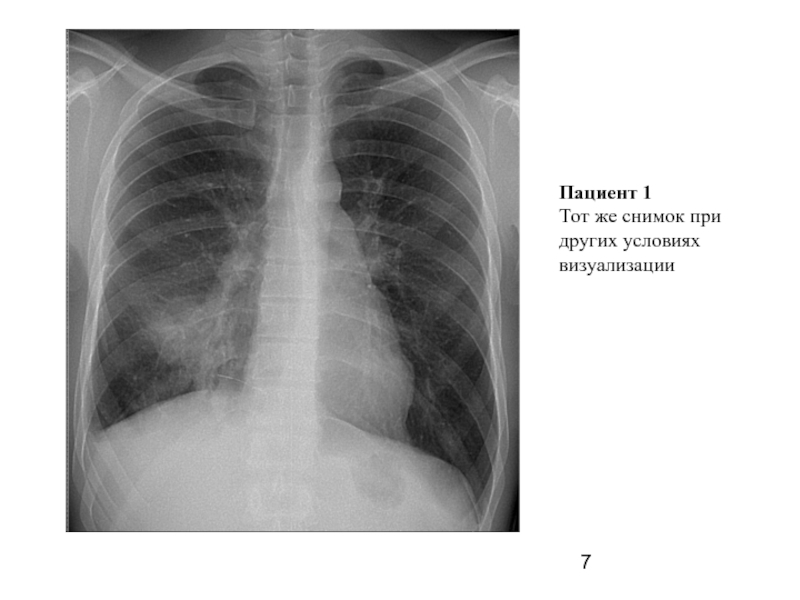

Слайд 7Пациент 1

Тот же снимок при других условиях

визуализации

Слайд 8Пациент 1

Слайд 6Пациент 1

(прямой снимок)

Описание:

справа в S-10 участок инфильтрации легочной ткани без четких

контуров.

Правый корень расширен, структурность снижена. Справа на границе нижнего

средостения на уровне D-10 определяется инородное тело металлической плотности, линейной формы, длинной 31 мм, окруженное

плевро-медиастинальными

спайками.

Заключение:

правосторонняя сегментарная S-10 пневмония. Металлическое инородное тело средостения (плевральной полости?) справа.